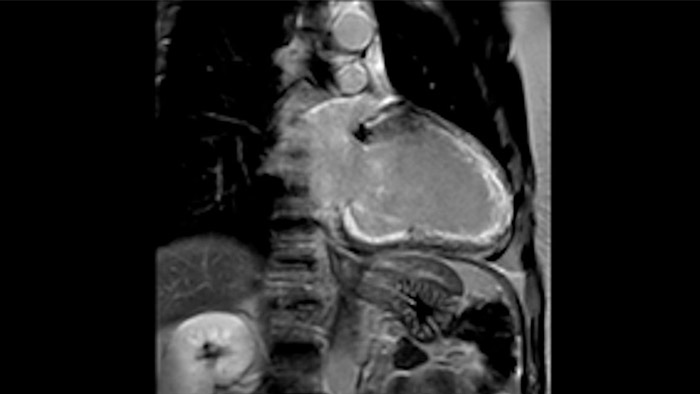

Comprehensive cardiac MR imaging

Diagnostic and prognostic utility of cardiac MR is increasing. Assess the anatomy and function of the heart using cine acquisitions, acquire information about perfusion and viability of the cardiac tissue, visualise potential edema with black blood sequence, access and even quantify tissue characterisation with CardiacQuant.

Visualize and evaluate blood flow

Visualise and evaluate blood flow

IntelliSpace Portal MR Caas5,6 4D Flow post-processing solution enables generation of 3D volume reconstructions, to visualise and evaluate blood flow in cardiovascular structures, including heart valves, chambers, and vessels, based on cardiovascular MR 4D Flow imaging.